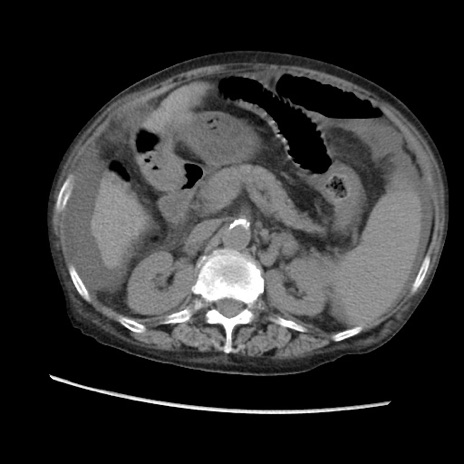

矢状断像

【症例】80歳代 女性

【主訴】腹部膨満感

【現病歴】他院にて肝硬変にてフォロー中。1週間前から便秘、腹部膨満感、臍部腫瘤あり受診となる。

【既往歴】肝硬変

【身体所見】腹部膨隆あり、皮膚変化なし、疼痛なし。

【データ】WBC 4600、CRP 0.25